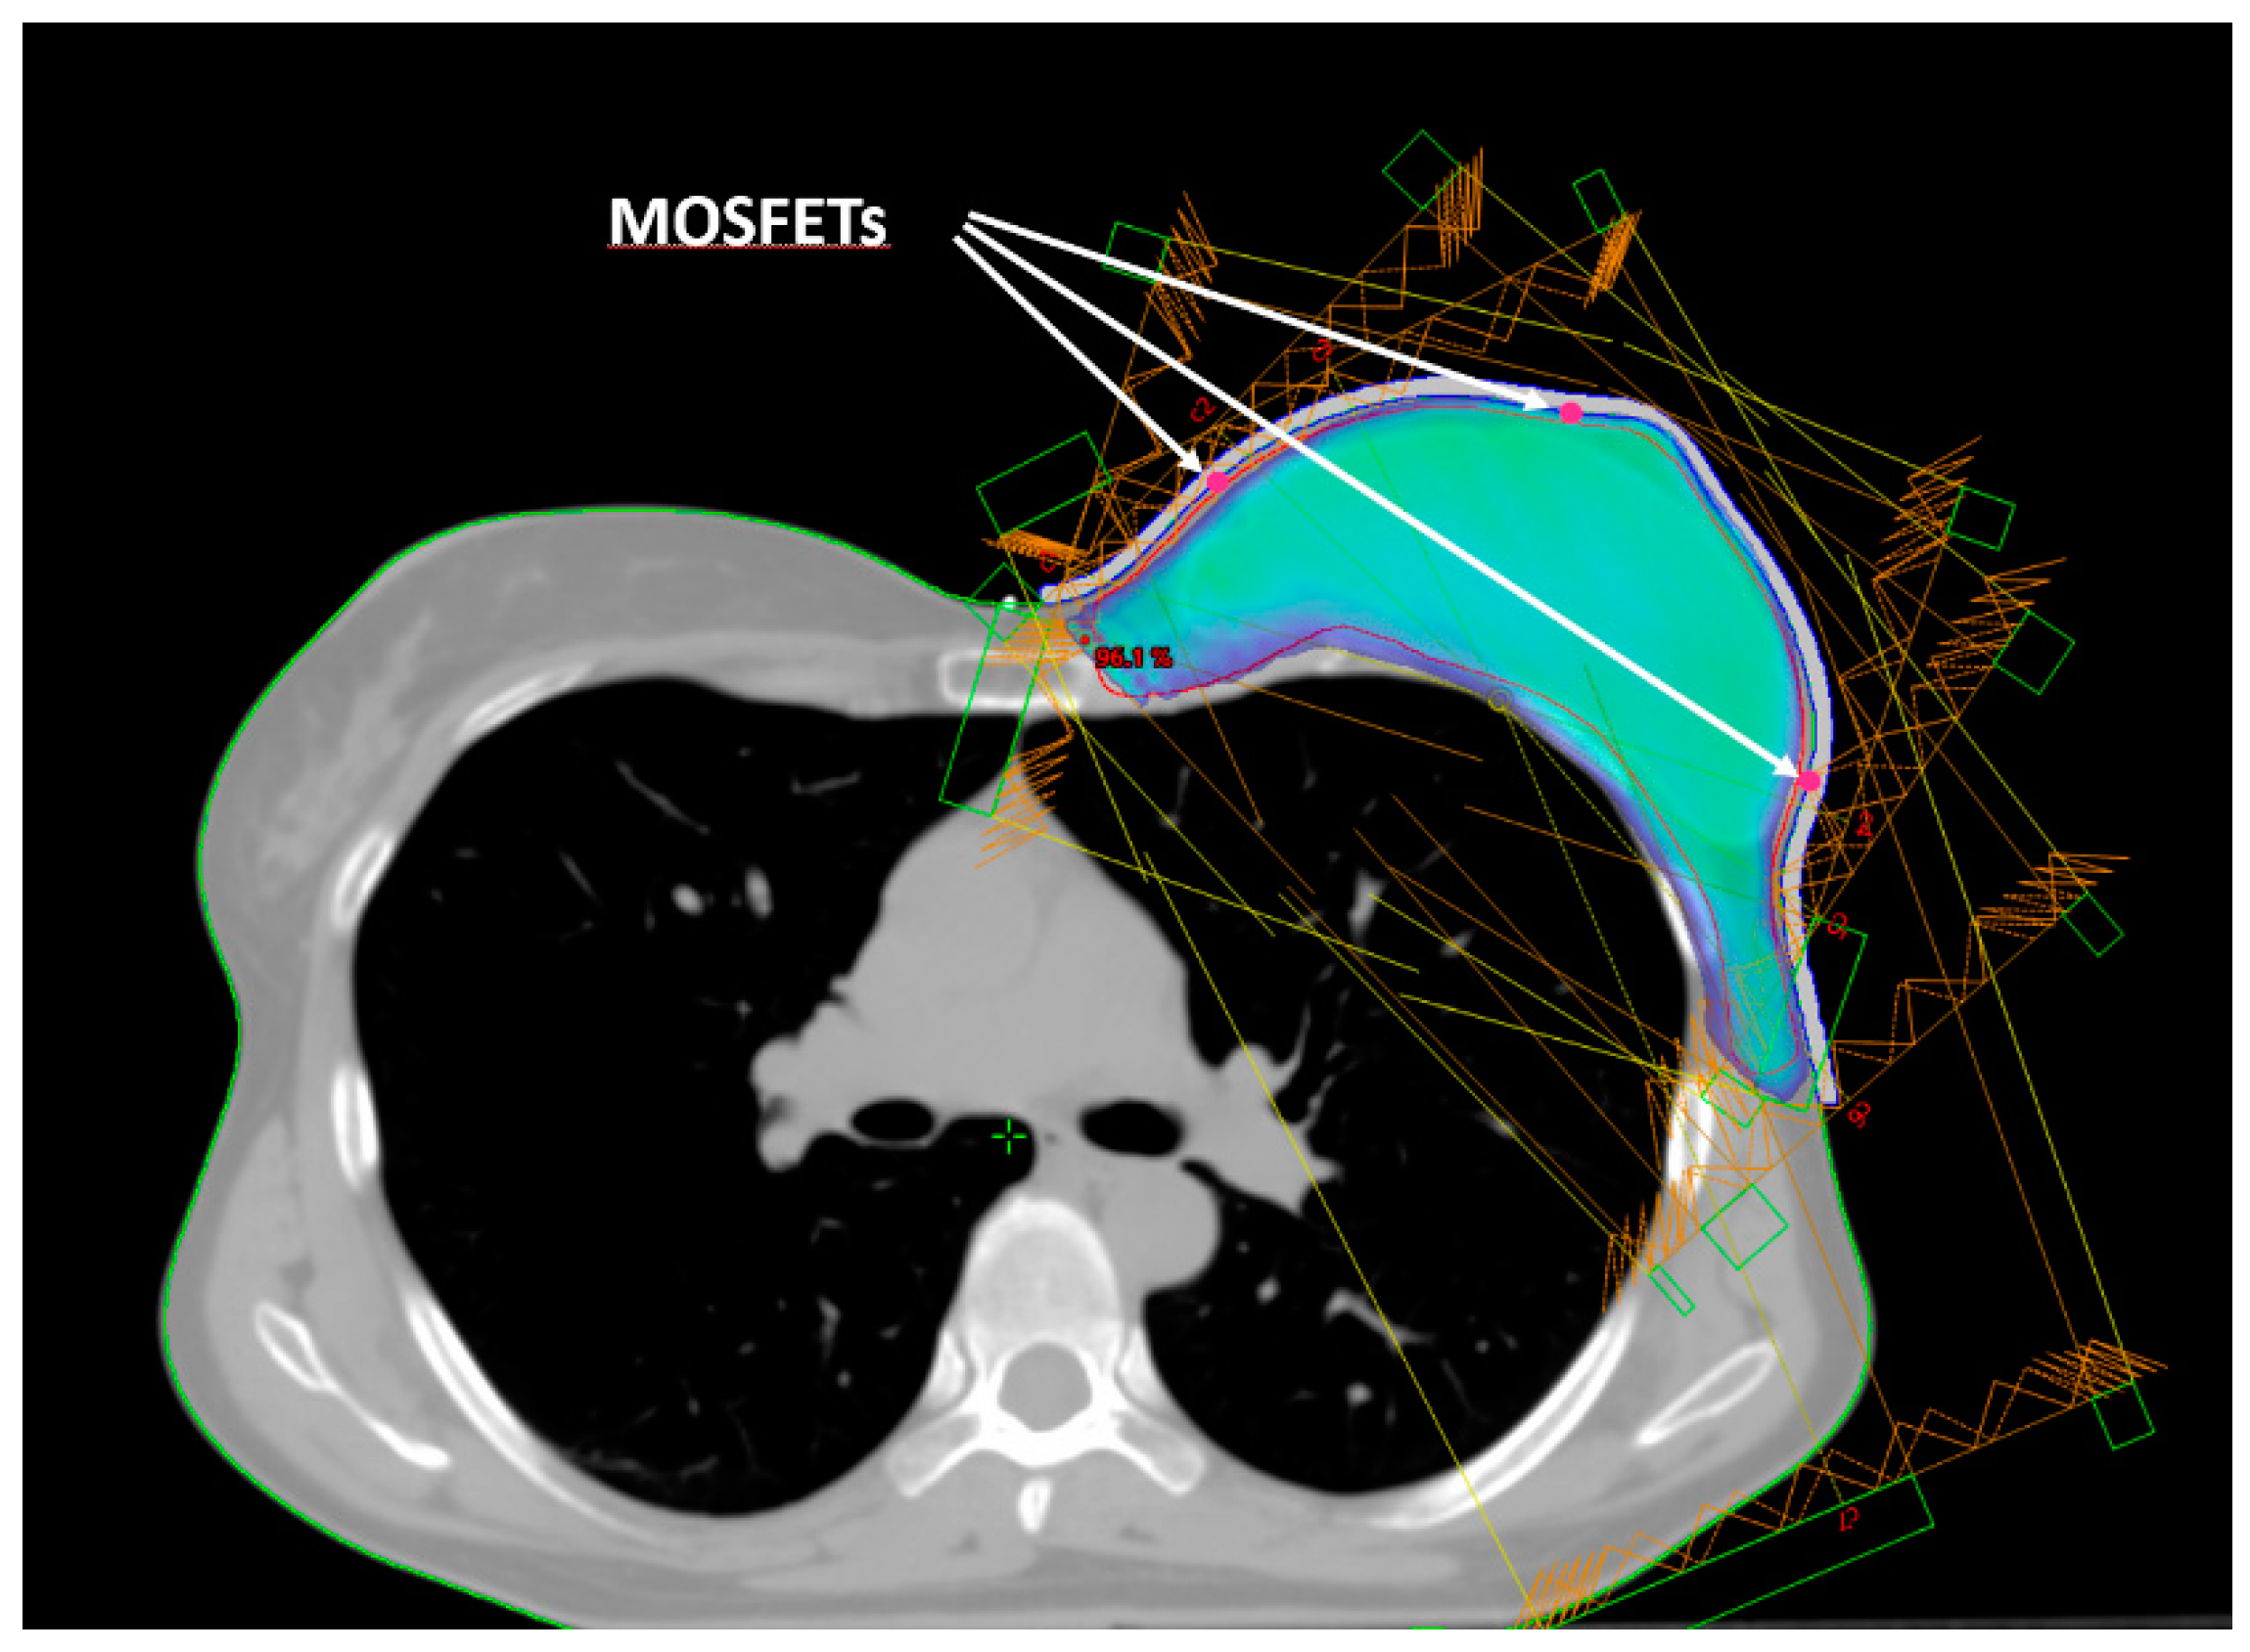

Five small spherical ROIs were freehand-contoured onto the patients’ CTs at the skin–bolus interface at the positions where the dose was planned to be evaluated. The five ROIs were subtracted from the bolus ROI, generating five holes at its inner surface, which served as suitable housings for the positioned MOSFET dosimeters (Figure 2). Thus, for the following dosimetric evaluation, the position of the MOSFETs at the bolus inner surface corresponded to the ROIs contoured on the TPS. Figure 1 shows the five chosen positions: A—cranial; B—central; C—caudal; D—medial; and E—external.

Figure 2.

Beam arrangement for IMRT dose delivery. Isodose of 95% of the prescribed dose. The arrows indicate the positions (red dots) of the three mid-height MOSFETs (E, B, D).